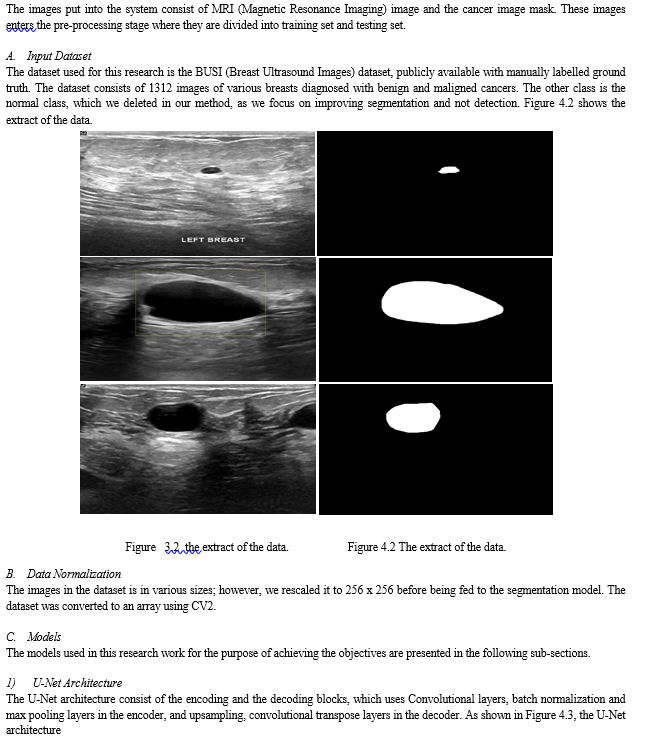

The experiments carried out in this research considered Jaccard, F1 score, recall, precision, accuracy and F2 measure as metrics. Also, we considered the model size for evaluation. As shown in Figure 4.1, the output of each segmentation model is visualized, and it can be seen that the segmentation obtained by the proposed model looks more similar to the ground truth mask. This was also validated, as shown in Table 4.2, where the performance of the proposed model outperformed the U-Net benchmark, and the baseline modified U-Net. This shows that by adding the squeeze and excitation block in our proposed model right after the contraction layer, more discriminant features were learnt.

The visualization of the metrics were presented in Figure 4.2 to Figure 4.7. Also, in Table 4.3, the model size of the three segmentation models were presented. The results showed that the proposed model had a 7.36 million parameters, which is high when compared to the benchmark U-Net. However, when compared to the baseline model which has 19.07 million parameters, the size of our proposed model is quite small, given that the proposed model outperformed the U-Net and the baseline U-Net, with few model complexity.